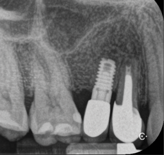

Fig 3. Intraoperative radiograph demonstrating apical resection of implant and tooth.

Figure 3

Report of a case. A 45-year-old male patient was referred with pain, redness, and swelling around an implant in the position of the maxillary right second premolar. The implant had been in clinical function for 3 years. The patient had a history of endodontic treatment and tooth loss and subsequent implant treatment in the region. Radiographic examination showed a radiolucency around the apical portion of the implant and the adjacent tooth. The implant was clinically stable and the neighboring tooth No. 4 was considered to have a periapical lesion. Initially, the patient received antibiotics (clindamycin 300 mg, three times daily) and was followed up for 2 weeks. After this, the patient was scheduled for surgical exploration of the implant area. Treatment comprised elevation of a full-thickness flap, curettage of the apical lesion, irrigation with saline, and removal of the apical portion of the implant and apicoectomy of the adjacent tooth (Figure 3 and Figure 4), including a guided bone regeneration (GBR) procedure with a cancellous particulate allograft and 20 mm x 30 mm pericardium membrane. Granulation tissue was sent for histopathology analysis, which revealed a periapical inflammatory infection. At the 4-month follow-up increased radiographic bone density could be observed consistent with the formation of bone not only around the implant apex but also along the root of tooth No. 5 (Figure 5).